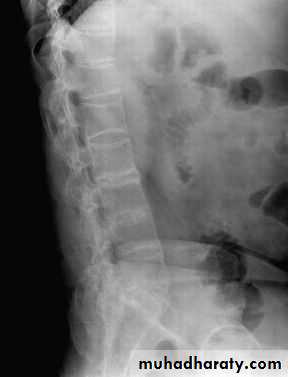

Lateral thoracolumbar spine Xrays may show anterior ‘squaring’ of vertebrae due to erosion and sclerosis of the anterior corners and periostitis of the waist.

Bridging syndesmophytes may also be seen. These are areas of calcification that follow the outermost fibres of the annulus

Investigations

In advanced disease, ossification of the anterior longitudinal ligament and facet joint fusion may also be visible. The combination of these features may result in the typical ‘bamboo’ spine.